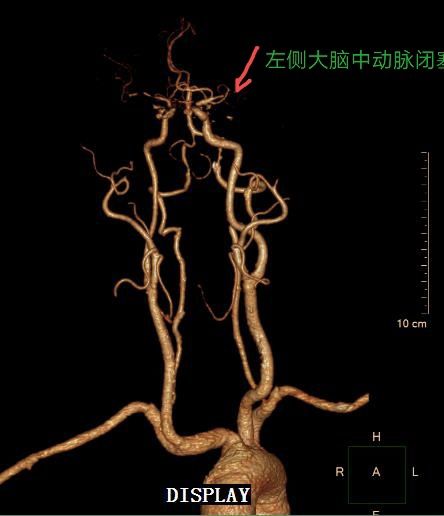

急诊头颅CTA:左侧大脑中动脉闭塞,右侧大脑中动脉重度狭窄或闭塞。